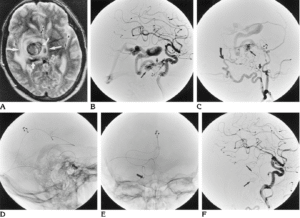

- Imaging Tests: Imaging tests such as CT scans or MRIs visualize the brain and detect the presence of an aneurysm. A CT or MR angiogram may be specifically used to get a detailed view of blood vessels.

- Coiling: A catheter is inserted into the blood vessel, and coils are placed inside the aneurysm to promote clotting and prevent bleeding.

- Endovascular Treatment: This minimally invasive procedure involves threading a catheter through blood vessels to the aneurysm and placing devices to block the aneurysm from blood flow.